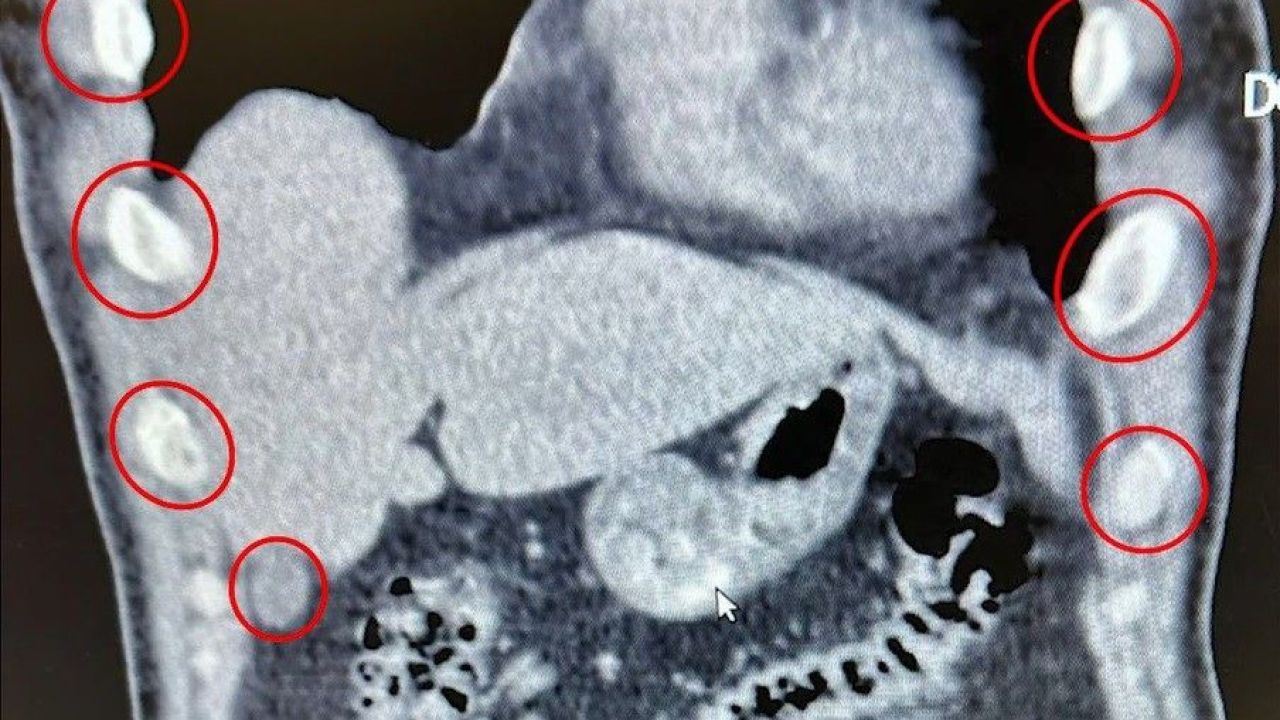

Bitlis İl Emniyet Müdürlüğü, uyuşturucu ile mücadele kapsamında gerçekleştirdiği operasyonda büyük bir sevkiyatı engelledi. Tatvan ilçesinde durdurulan bir yolcu otobüsünde seyahat eden yabancı uyruklu iki kişi, mideye gizledikleri 136 kapsül uyuşturucu maddeyle yakalandı.

Şüphelilerin sağlık kontrolleri sırasında yapılan tıbbi müdahalede, toplam 1 kilo 48 gram metamfetamin içeren 136 kapsülün yutularak taşındığı ortaya çıktı. Zanlılar, "Uyuşturucu Madde İmal ve Ticareti" suçlamasıyla gözaltına alındı. Emniyetteki işlemlerinin ardından çıkarıldıkları mahkemece tutuklanarak cezaevine gönderildi.